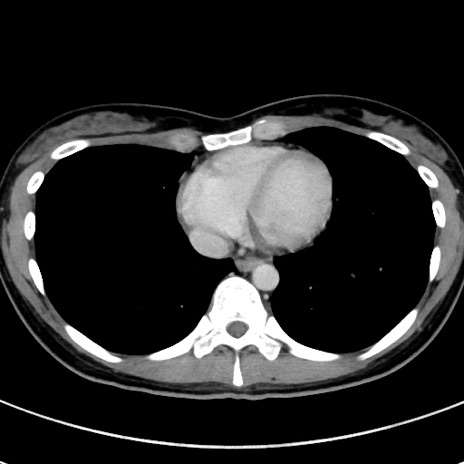

症例17(横断像)

【症例】20歳代女性

【主訴】嘔吐、下腹部痛

【現病歴】昨日夕食後に嘔吐し下腹部痛が出現。本日になっても嘔吐持続し改善しないため来院。

【身体所見】意識清明、BT 37.2℃、BP 108/67mmHg、腹部:平坦、やや硬、下腹部正中から右にかけて圧痛あり、反跳痛軽度あり、tapping pain(+)。

【データ】WBC 13600、CRP 14.94